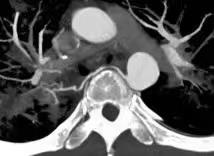

随着CT技术的发展,CT血管成像(CTA)的应用越来越广泛,本课题主要探讨支气管动脉CTA检查影响其阳性显示的主要因素以及本地区普通人群BA分布图。支气管动脉(BA)是肺支架组织的营养血管,其多发自胸主动脉,走行于纵膈间隙,攀附于支气管壁经过肺门进入肺组织,形成毛细血管网并营养周围组织。BA本身管径细小(1-2mm),走行迂曲,行程不定;起源、开口位置及数目变异大,若能在实施介入治疗前对BA的分布、形态及与疾病的关系有一全面了解,将对介入治疗提供重要帮助。

研究认为,支气管动脉作为肺部介入手术的主要靶血管,在实施介入手术前,对有肺部基础疾病的患者行支气管动脉CTA检查,支气管动脉能都得到阳性显示,同时能提供一个非侵入性评价支气管动脉及其肺部病变的有效方法。

因为支气管动脉起源变异明显,该科研课题的应用,术前能把支气管动脉的起源及走行显示的更清楚,更有利于提高手术成功率,减少术后复发的机会,降低医疗风险,是一种安全有效、经济实用的方法,该技术值得临床推广应用!